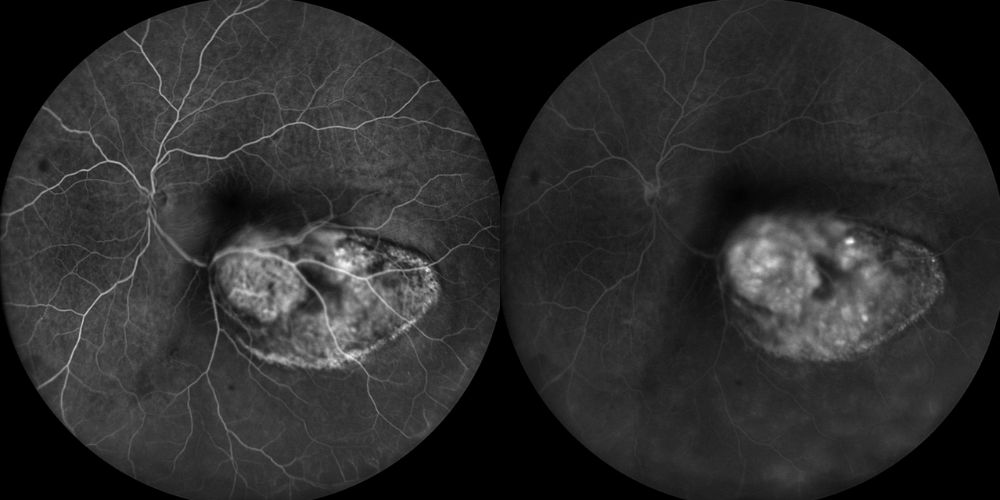

Fluorangiografia

Fluorangiografie